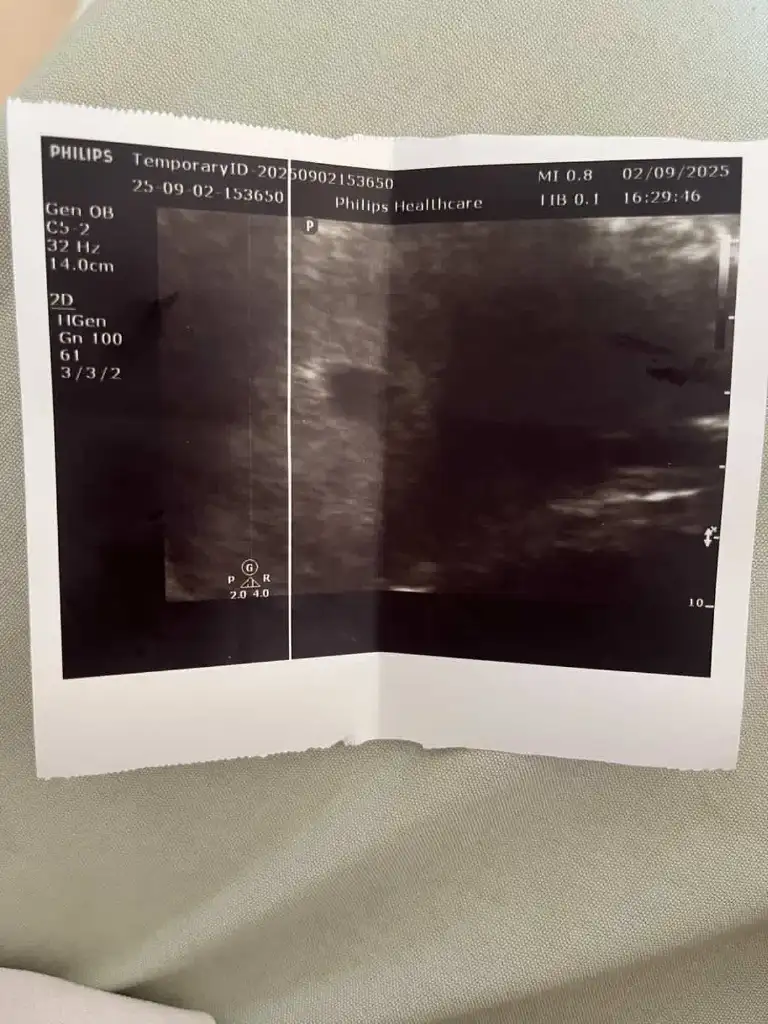

Arkadaşlar merhaba daha önce burada ultrason fotoğrafına bakıp cinsiyet tahmin edenleri görmüştüm benim içinde bi heyecan olur:) var mıdır tahmininiz normalde 12+4 üm ama ultrasonda 13 haftalık görünüyor

bana da bakabilir misiniz acaba 😍